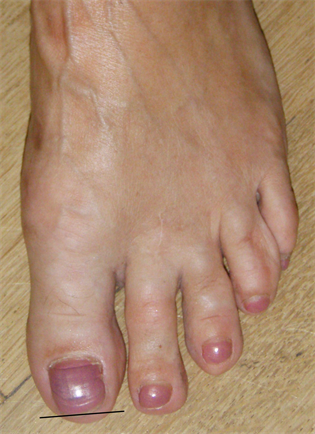

Figure 10. Patient Nr 2. Clinical appearance before the operation.

Figure 11. (a) Patient Nr. 2. Result after 7 years; (b) Medic ballerina for undisturbed walking with bulky dressing or swellings